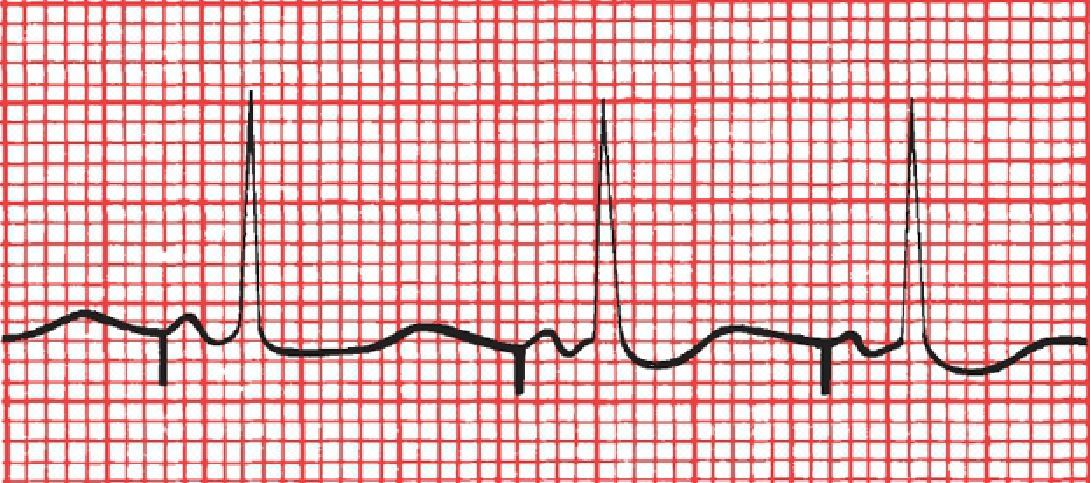

Is this NSR? If not, what is it?

First-degree AV block. Note the prolonged PR interval.